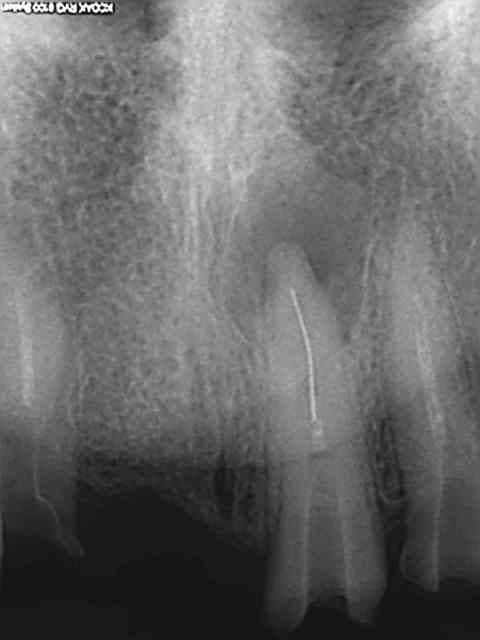

Bridge descellé, re-scellé plusieurs fois par plusieurs dentistes différents. la charte de bonne pratique est respectée (vu qu'on ne fait pas de prothèse) on re-scelle sur de la merde.

Bonjour l'odeur dans les canaux, Il fallait bien qu'il y en ai un qui y mette un terme.

Bien sur l'essentiel porte sur la ventilation des honoraires du bridge à refaire.

Je ne fais jamais de cathétérisme manuel, ca évite de casser des limes 15 de merde dans les canaux. d'ailleurs je ne sais pas ou elle est passée celle là, quelque part dans l'aspi je suppose.))))))

Reprise au R25 puis R40.

Charte de bonne pratique de merde, qui intéresse tout sauf la pratique. Ca m'énerve.